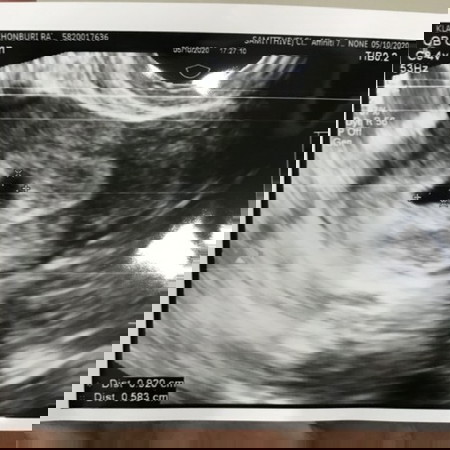

แม่ๆ รู้ว่าตัวเองตั้งครรภ์ตอนกี่สัปดาห์คะ ตอนที่รู้ว่าท้องรู้สึกยังไงกันบ้างคะ บ้านนี้รู้ตอนประมาณ 5 สัปดาห์ค่ะ 😊 ตรวจเองที่บ้านตอนห้าทุ่มขีดแดงชัดมาก เช้าอีกวันรีบไปโรงพยาบาลเลยค่ะ อัลตราซาวด์เจอถุงการตั้งครรภ์ แม่นี่มึนงงไม่หมดเลยค่ะ นี่เรากำลังจะเป็นเเม่คนเเล้วรึ🤣 #ท้องแรกคะ